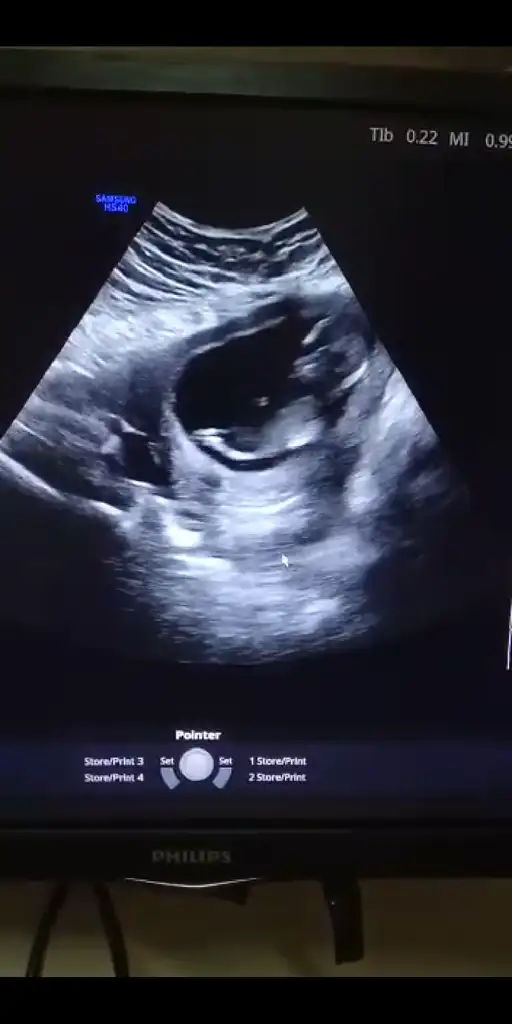

Nub yöntemine göre cinsiyet tahmini

Gittim canim dr kiz gibi dedi ama kesin soyleyebilmem icin 16.haftayi bekleyecegiz dedi ama nubu bana gore karsiya bakiyor onda da kesin konusmadi erkek olsa yanilma olmaz bu haftalarda ama bazen kizda yanilma olabilir bekleyelim dedi